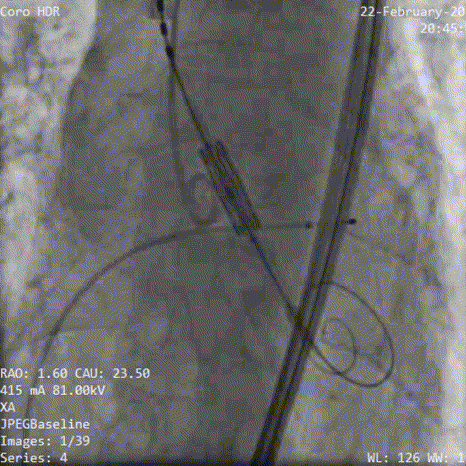

术中影像:

5.测量压差

6.造影提示瓣周漏,考虑瓣架形态再次后扩

7.加1cc后扩